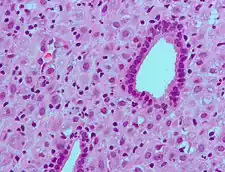

- Micrograph of chronic deciduitis. H&E stain.

The decidua has a histologically-distinct appearance, displaying large polygonal decidual cells in the stroma. These are enlarged endometrial stromal cells, which resemble epithelium (and are referred to as "epithelioid").

Its leukocyte population is distinct, with the presence of large endometrial granular leukocytes being predominant, while polynuclear leukocytes and B cells are scant.